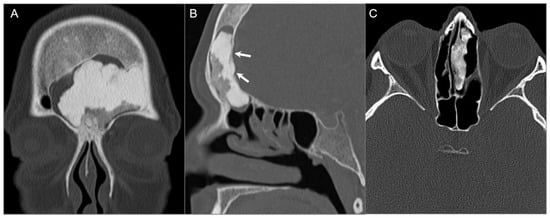

4.4.1. Chordoma

4.4.2. Chondrosarcoma